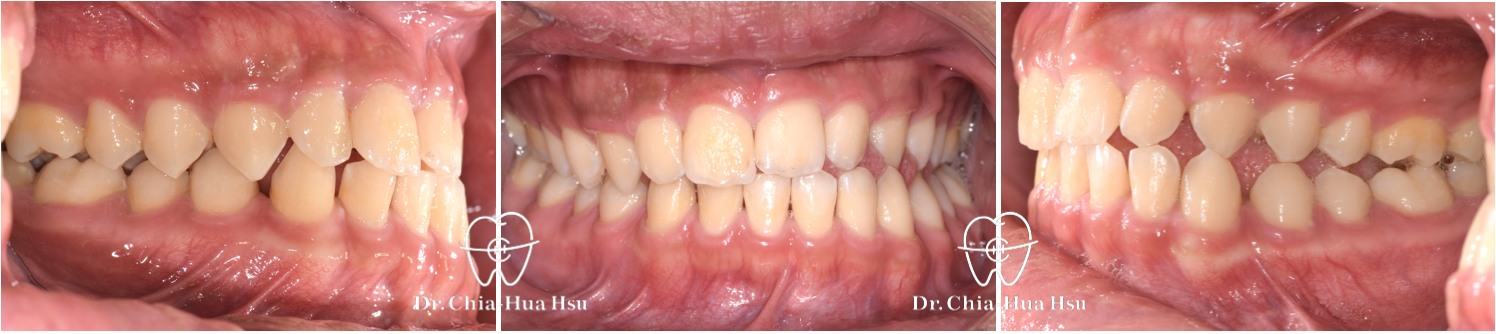

咬合不正、錯咬、咬合平面傾斜

青少年矯正 | 金屬矯正 | 上顎擴弓 | 非拔牙治療

治療前

治療後